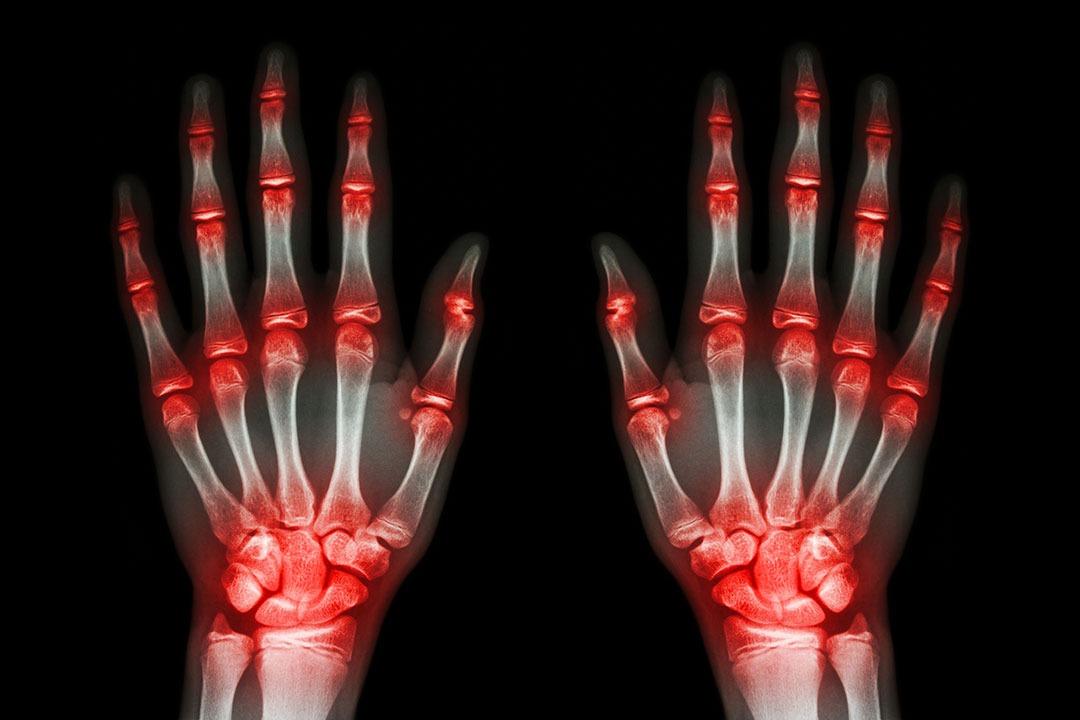

Tako je u moj život, pre dvadeset dve godine, stigao artritis, reumatodni artitis.

Dobila sam odgovor koji i danas slušam i od drugih osoba bolesnih od ove bolesti: to je bolest u kojoj moj organizam napada moj organizam, ne zna se šta je, zašto je, traje doživotno, ali se od nje ne umire. Prokletstvo autoimune bolesti.

Prolaze godine (nisam dugo na posebnom režimu ishrane), i ja primetim da mi se odjednom krive prsti na desnoj šaci. Šta je sad to? Kaže doktor – fokina peraja. Ju, zar je to moguće? Moguće, da, uostalom postali smo od čovečje ribice… a i ja sam rođena u znaku Ribe. Na žalost, moje šake će zauvek ostati takve.

Posle mnogo godina ta ista peraja više liče na nekakva krila. Žena-ptica. Zašto, pitam novog doktora? Morate da uzimate lek metotreksat, kaže doca. Šta je to? To je uobičajeni lek za ovu bolest. Je l’ citostatik? Jeste, ali nije ništa u odnosu na pravi od 50 mg. Samo 10. Doktore, je l’ opada kosa? Pa malo…da.